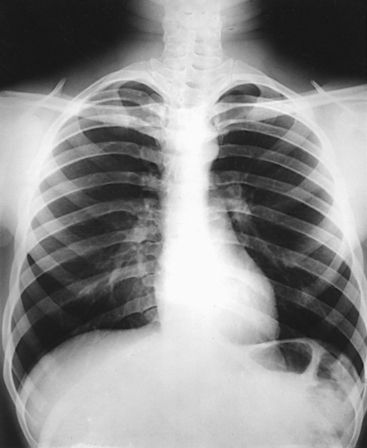

Structures shown: PA projection of the thoracic viscera shows the air-filled trachea, the lungs, the diaphragmatic domes, the heart and aortic knob, and, if enlarged laterally, the thyroid or thymus gland (Fig. 10-32). The vascular markings are much more prominent on the projection made at the end of expiration. The bronchial tree is shown from an oblique angle. The esophagus is well shown when it is filled with a barium sulfate suspension.

Structures shown: An AP projection of the thoracic viscera (Fig. 10-51) shows an image similar to the PA projection (Fig. 10-52). Being farther from the IR, the heart and great vessels are magnified and engorged, and the lung fields appear shorter because abdominal compression moves the diaphragm to a higher level. The clavicles are projected higher, and the ribs assume a more horizontal appearance.